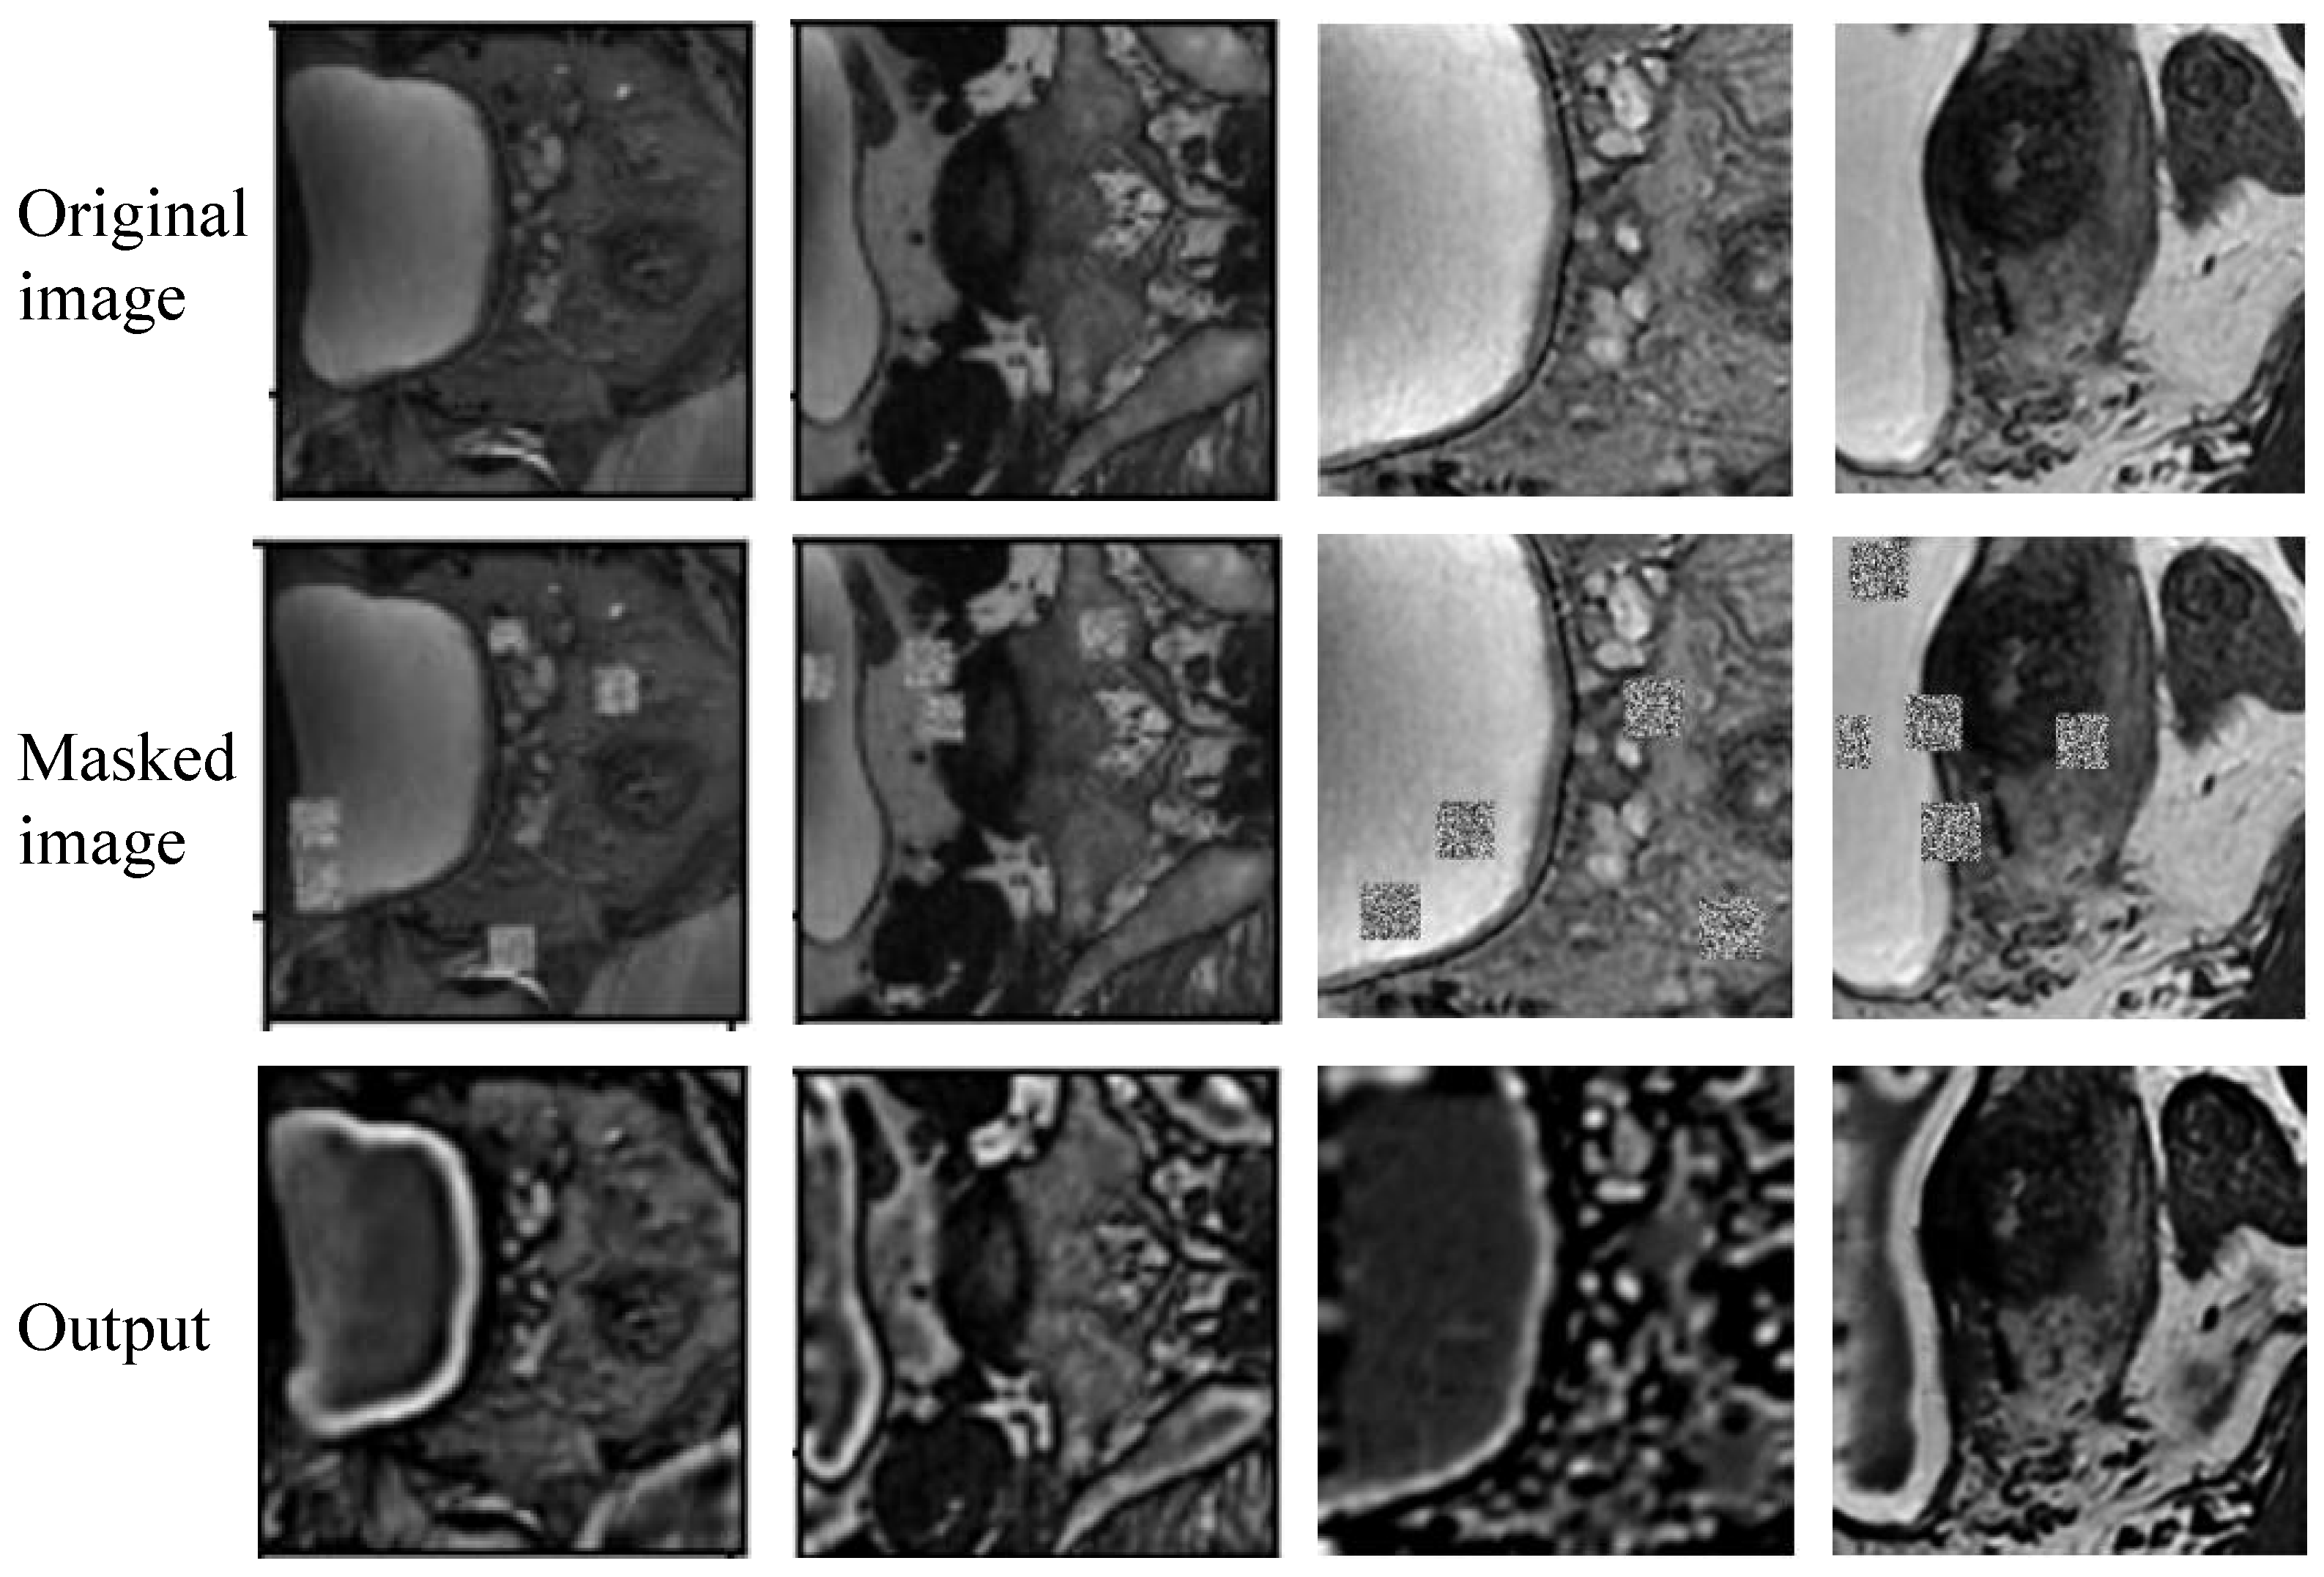

An overview of the two-step wall-enhanced self-supervised pre-training stage is shown in Figure 2. In the first step, image processing is applied to prepare the training data for self-supervised learning. Specifically, the images are cropped randomly to image patches with a size of 256 × 256 , then the masked image patches are obtained by adding noise at random holes. We set the number of holes to 5–10 and the size to 15–20. In the second step, these masked image patches and the cropped image patches are used as training data for self-supervised learning. Two different masked image patches obtained from the same cropped image patch are input into the reconstruction network, then the network is trained via minimization of the contrast and reconstruction loss.

3.4.4. Reconstruction Results

Figure 9 displays the reconstruction results obtained during the wall-enhanced self-supervised learning stage. It is evident that the reconstructed images enhance the delineation of the bladder wall, increasing the contrast between the bladder wall and surrounding tissues. This enhancement indicates that the network effectively captures the boundary information of the bladder wall, thereby enhancing the capability of the subsequent bladder wall segmentation model to accurately extract boundaries.

Figure 2. Overview of wall-enhanced self-supervised pre-training method with contrast consistency and reconstruction observation losses. Step 1: Prepare training data for image reconstruction by applying random crop and mask. Step 2: Pre-train the model via self-supervised learning constrained by contrast consistency and reconstruction observation losses.

Figure 9. Reconstruction results in the wall-enhanced self-supervised learning stage.